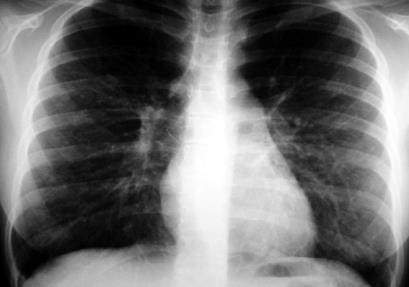

38) Indique que le sugiere la siguiente imagen:

Fig. 4

TBC

Bronquitis crónica.

Neumonía.

Enfisema.